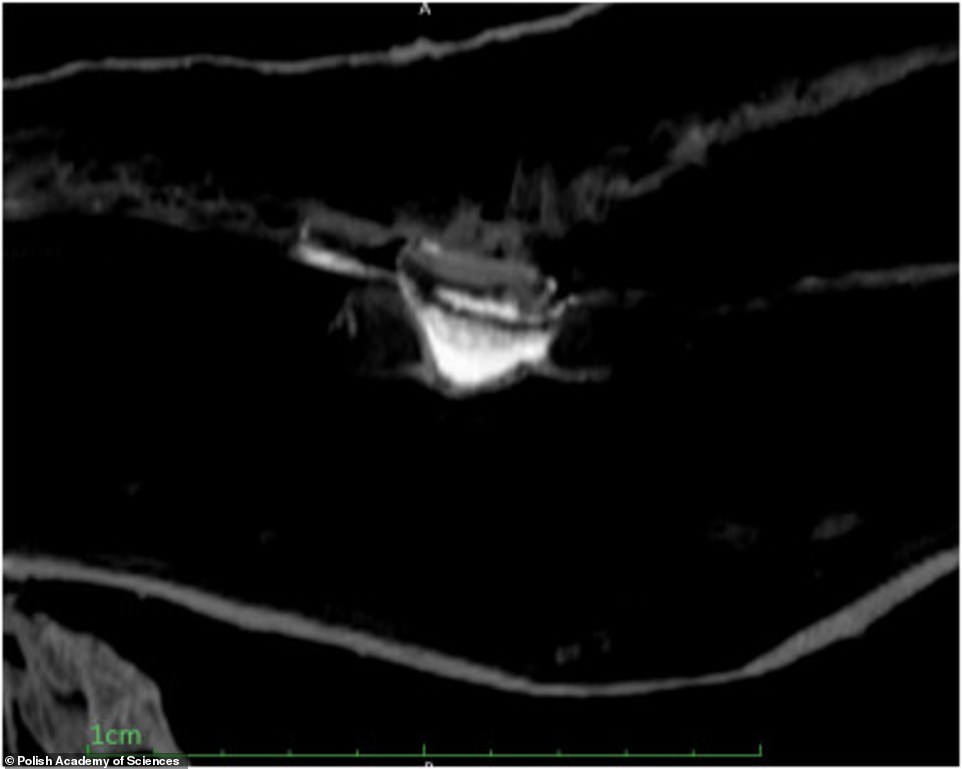

Вчені використовували безліч різних фільтрів, щоб вивчити мумію сканером, не торкаючись до неї. Було встановлено, що жінка перебувала приблизно на 26-28 тижні вагітності, плід знаходиться в положенні ембріона, стать дитини визначити не вдалося.